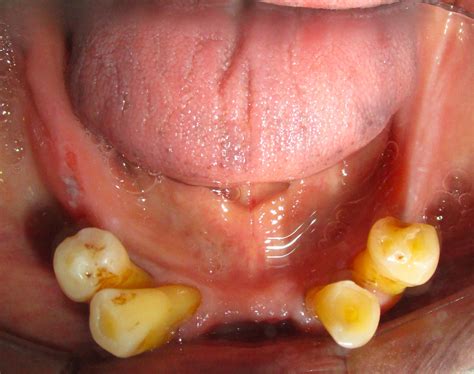

Edentulous arch maxilla photographs | PPT

Edentulous arch maxilla photographs | PPTX